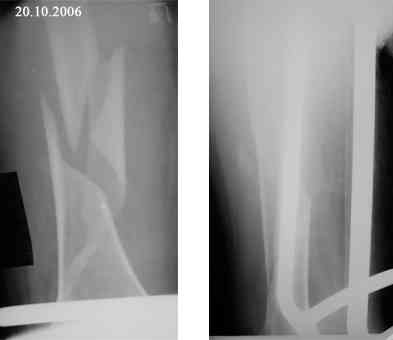

Женщина 66 лет 15.10.2006 получила закрытый окольчатый перелом правой бедренной кости в с\з-н\з со смещением отломков. 17.10.2006 доставлена в травм.отделение (2-е суток лежала одна дома). При поступлении наложено скелетное вытяжение за бугристость большеберцовой кости - груз 5 кг, затем увеличен до 7 кг. Схематические рисунки контрольных Р-грамм прилагаются (прошу прощения за отсутствие Р-грамм, постараюсь "донести").В связи с отсутствием материальных средств и "удовлетворительным" положением отломков решено было скелетное вытяжение оставить как окончательный метод лечения. На 20.11.2006 отека правого бедра нет, пальпаторно умеренная болезненность в месте перелома, крепитации отломков нет (и по-видимому не было изначально),подвижность в месте перелома сохранена, но не выражена. Двигательных, чувствительных и трофических расстройств правой нижней конености нет. Уважаемые коллеги! Какова дальнейшая тактика в случае вероятной интерпозиции тканей? Больная "кровавое" оперативное лечение не "потянет" материально. Даст ли в данном случае что-то АВФ закрыто?

Представляю вашему вниманию снимки в динамике